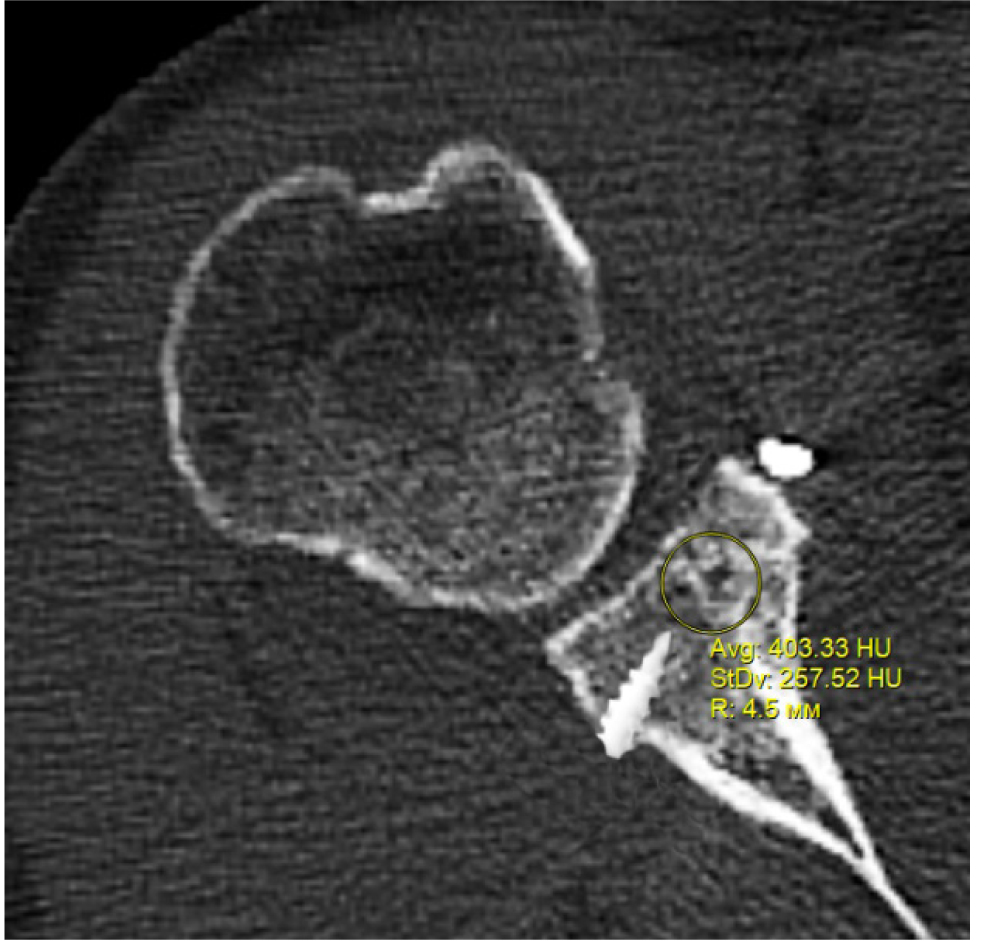

В программном обеспечении, на аксиальных КТ срезах оперированного плечевого сустава, выбирали инструмент «круг», который позволял посчитать среднюю плотность тканей внутри круга в единицах Хаунсфильда. Шкала единиц Хаунс-филда (HU) – шкалалинейного ослабления излучения по отношению к дистиллированной воде, рентгеновская плотность которой была принята за 0 HU (при стандартных давлении и температуре). Круг устанавливали таким образом, чтобы одна его половина была заполнена тканью гленоида, вторая половина тканью трансплантата (рис. 1–3). Оценивали плотность тканей над проксимальным винтом, между винтами, под дистальным винтом. Полученные данные анализировали с помощью пакета Microsoft Excel.

Рис. 3. Оценка плотности ткани над проксимальным винтом

Через 3 месяца после оперативного лечения по данным анализа КТ срезов были получены следующие результаты: плотность ткани над проксимальным винтом составили (424 ± 24,3) HU, между винтами (460 ± 23,4) HU, под дистальным винтом (587 ± 49,1) HU. Спустя 6 месяцев после операции плотность ткани над проксимальным винтом составили (320 ± 28,7) HU, между винтами (424 ± 36,2) HU, под дистальным винтом (623 ± 33,4) HU. Через 12 месяцев после операции показатели были следующие над проксимальным винтом (276 ± 22,1) HU, между винтами (387 ± 31,1) HU, под дистальным винтом (662 ± 43,2) HU (таблица).